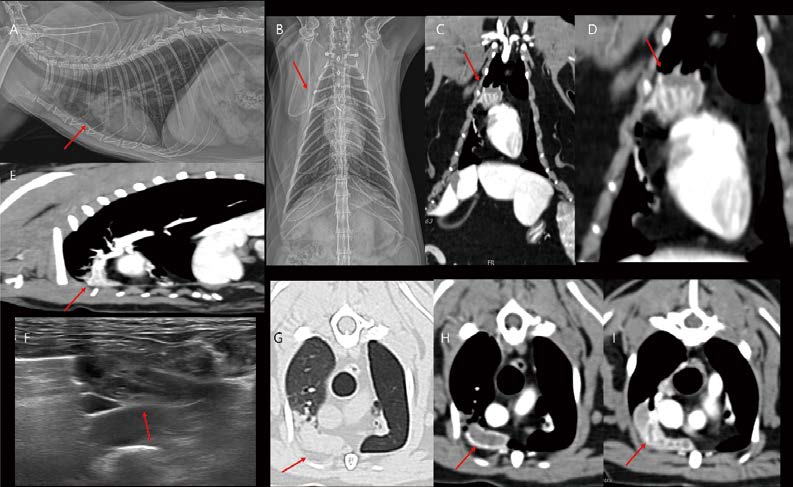

9살 중성화 수컷 5.6kg DSH cat이 3주 전부터 좌측 전지 부종으로 내원하였습니다. 좌측 전지 방사선 검사에서 3rd, 4th digits 주변으로 심한 연조직 밀도 부종이 관찰됩니다(I). 고양이에서 전지, 특히 3rd, 4th digits의 병변은 feline lung digit syndrome(원발성 폐종양, 주로 bronchogenic adenocarcinoma에서 호흡기 관련 증상은 없다고 하더라도, 하나 이상의 digit로 전이가 진행된 임상적 상태)이 고려됩니다. 흉부 방사선 검사 외측상에서 심장과 횡격막 사이 다소 밀도가 높은 tubular bronchiectasis with mucoid impaction? tubular mass? 음영이 관찰됩니다. 또한 위식도연접부 앞쪽으로 연조직 밀도 종괴? 음영이 횡격막을 배경으로 관찰됩니다. VD view, DV view 모두 위식도연접부 앞쪽으로 연조직 밀도의 둥근 음영이 횡격막을 배경으로 한계 불명확하게 관찰됩니다(A, D, E, 붉은 화살표). 일반적인 흉부 초음파 view로는 병변이 잘 관찰되지 않아, 복강을 통해 위식도연접부 내측을 스캔하니 이질적 저감쇠 종괴가 관찰됩니다(H). CT 검사를 진행하였고, 심장과 횡격막 사이 관찰되었던 영역은 atelectasis, bronchiectasis with mucoid impaction 양상으로 관찰됩니다(C). 위식도연접부 앞쪽으로 작은 석회화 음영 동반한 커다란 종괴가 관찰됩니다(B, F, G). 보호자님께서 전지 digit 절제를 원하셔서 진행하였고, 세포조직학적 검사에서 margin은 complete하였고, adenocarcinoma로 확인되었습니다. 수술 후 palladia로 관리하던 중, 내원하지 않으셨으나, 4개월 뒤 수술한 좌측 전지의 다른 digits, 반대편 전지 digits, 전신적으로 multifocal muscles의 전이성 병소가 확인된 상태로 사망하였다고 전달받았습니다.

[대한수의사회지 24.png

고양이 원발 폐종양 인접은 림프절 또는 흉강내 전이 외에도 extrapulmonary metastasis(e.g., digits) 등 다양한 부위로 전이가 발생할 수 있습니다. 그리고 extrapulmonary metastasis 발생률과 원발 폐종양 크기는 연관성이 있어서, 즉 원발 폐종양이 어느 정도 크기가 커질 경우 extrapulmonary metastasis가 발생합니다. 이 환자의 경우 흉부 방사선 검사에서 심장과 우측 횡격막 사이 accessory lung lobe으로 생각되는 영역의 비정상 소견은 CT에서 크기가 크지 않은 atelectasis 영역으로 관찰됩니다. 위식도연접부 앞쪽 종괴는 CT에서 크기가 어느 정도 있음에도 불구하고, 흉부방사선에서는 횡격막에 가려 쉽게 놓치기 쉽습니다. 폐야는 횡격막을 지나 간엽과 어느 정도 overlapping된다는 점을 잊지 않아야 합니다. 특히 고양이에서 폐종양은 들키지 않게 잘 숨어 있는 것 같습니다.